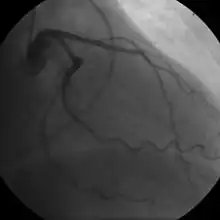

Coronary angiogram of a female

The diagnosis of CAD depends largely on the nature of the symptoms and imaging. The first investigation when CAD is suspected is an electrocardiogram (ECG/EKG), both for stable angina and acute coronary syndrome. An X-ray of the chest, blood tests and resting echocardiography may be performed.[73][74]

For stable symptomatic patients, several non-invasive tests can diagnose CAD depending on pre-assessment of the risk profile. Noninvasive imaging options include; Computed tomography angiography (CTA) (anatomical imaging, best test in patients with low-risk profile to "rule out" the disease), positron emission tomography (PET), single-photon emission computed tomography (SPECT)/nuclear stress test/myocardial scintigraphy and stress echocardiography (the three latter can be summarized as functional noninvasive methods and are typically better to "rule in"). Exercise ECG or stress test is inferior to non-invasive imaging methods due to the risk of false negative and false positive test results. The use of non-invasive imaging is not recommended on individuals who are exhibiting no symptoms and are otherwise at low risk for developing coronary disease.[75][76] Invasive testing with coronary angiography (ICA) can be used when non-invasive testing is inconclusive or show a high event risk.[74]